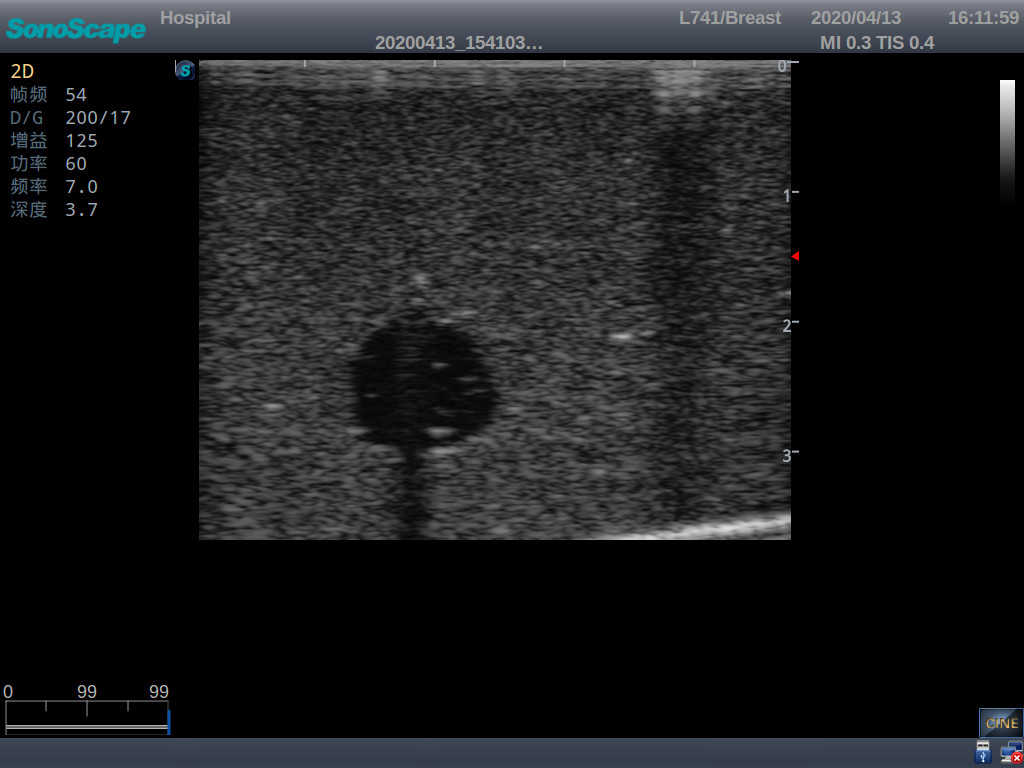

2)  Each model contains 8 space-occupying lesions of varying sizes, different in touch, elasticity and ultrasonogram

4) Biomimetic material allowing users to see clear and real normal tissues and space-occupying lesions that are hyperechoic, hypoechoic and isoechoic as they would see in the clinical environment